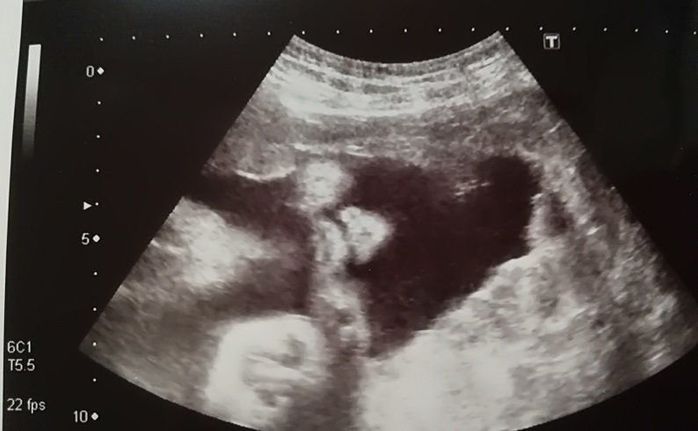

妊娠18週目のエコー写真

頭がくっきり。そして足を曲げている様子もわかります。5カ月目に入り、ようやくつわりがおさまりました。早速、やりたかったマタニティーヨガに挑戦。結果は、お香の匂いと逆転のポーズで吐いてしまいました。ちょっと調子に乗りすぎたようです。でも、ちょうど紅葉の季節にさしかかり、一泊旅行に出かけるなど楽しいことがたくさんできました。